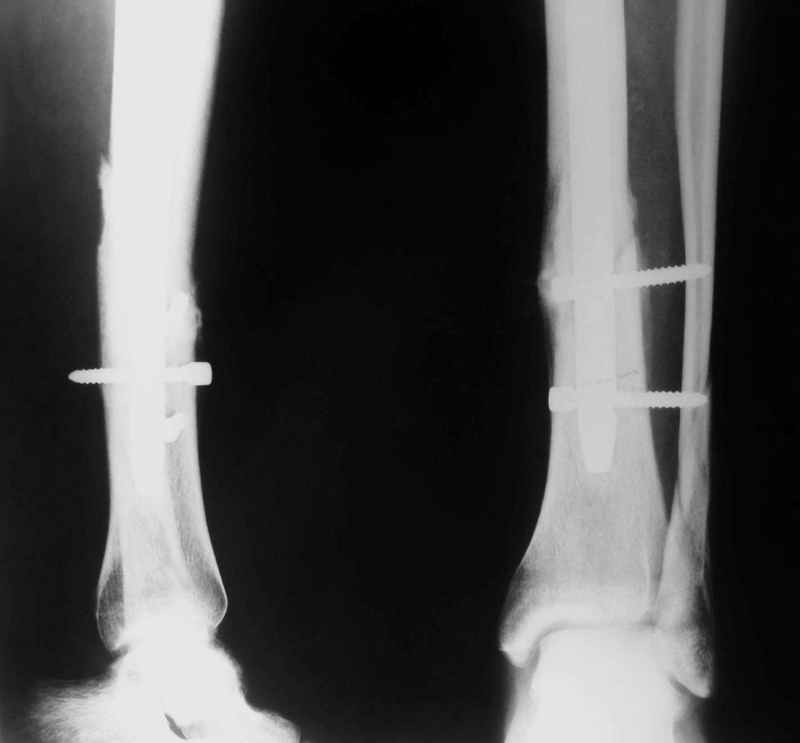

Рентгенограмы

Не удается отправить первичные снимки. А что скажите по имеющимся?!

Выполненный остосинтез нестабилен. Штифт надо заменить по "размеру" на солидный, дистльно три запирающих винта. Успехов!

Перелом спиральный, то есть низкоэнергетический, так что со сращением дело обстоит уже неплохо, лишь бы "костоеда" не развилась. Отломки выглядят уже стабилизированными костной мозолью, так что довводить винты, наверно, уже незачем. Разве что при клинической оценке подвижность еще есть - тогда можно для стабилизации наложить простейший аппарат, не опасаясь контакта его элементов с гвоздем, поскольку места в дистальном метафизе оставлено более чем достаточно.

С Александром согласен, нет необходимости делать дополнительные усилия для сращения, не большая компрессия аппаратом из двух колец и полная нагрузка доделает работу.